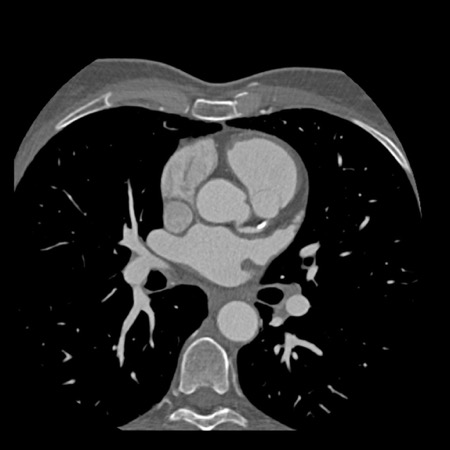

case 1 – CAD-RADS 2/P1

First, scroll through the scan.

Not all images are included. Some images without any abnormalities are skipped

from the series.

How would you describe the findings on the coronary CTA?

The findings are:

- Agatston score of

this patient was 14 (P1). Please, also note the calcification of the aortic valve. - Some partially

calcified and calcified plaques are present in the LAD with mild stenosis

(25-49%). - Calcified-plaque in

the LCX causing minimal stenosis (<25%). - Non-calcified

plaque in the distal RCA causing minimal stenosis (<25%). - This patient classifies

as CAD-RADS 2/P1, which means no further workup is needed.